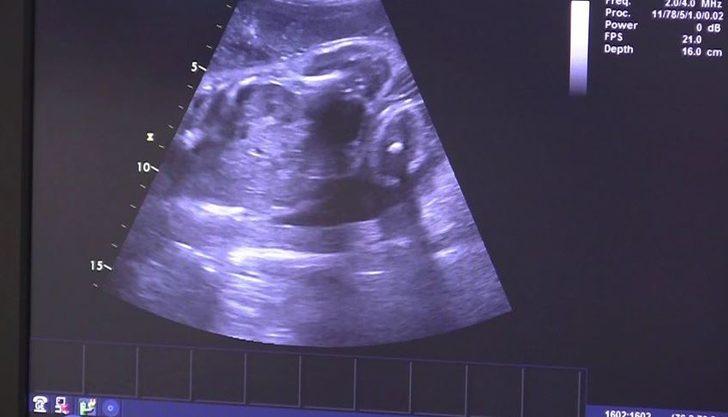

Çekya’da 21 Nisan günü felç geçiren ve 16 haftalık hamile olan Mrtvá Eva (27) hastaneye kaldırıldı ancak tüm müdahalelere rağmen beyin ölümü gerçekleşti. Doktorlar, Eva’yı makinelere bağlı tutarak bebeğin anne karnında gelişimini tamamlamasını sağladı. 15 Ağustos’ta bebek doğdu, ancak Eva yaşamını yitirdi.

Nisan ayında hastaneye kaldırılan Eva’nın karnındaki fetüs, yaklaşık 300 gram ağırlığındaydı. Brno Üniversite Hastanesi’ndeki doktorlar, hastanede makinelere bağlı olarak 3,5 ay geçiren Eva’yı ameliyathaneye aldı. Sezaryen ile dünyaya gözlerini açan Eliska bebeğin, doğduğunda 2 kilo 130 gram olduğu ve sağlık durumun iyi olduğu açıklandı. Doktorlar, Eliska’nın, felç geçiren bir anneden doğan bebekler arasında kilosu en yüksek olanlardan birisi olduğunu belirtti.

21 Nisan günü Vojtech, eve geldiğinde eşi Eva’yı bilincini kaybetmiş şekilde buldu. Helikopterle hastaneye kaldırılan Eva, bilinçsiz bir durumda, dolaşımı sabit tutularak ve vücut sıcaklığını azaltılarak, Resüsitasyon ve Yoğun Tıp Bölümüne alındı. Karnındaki fetüsün kalbinin de düzenli bir şekilde attığı tespit edildi.